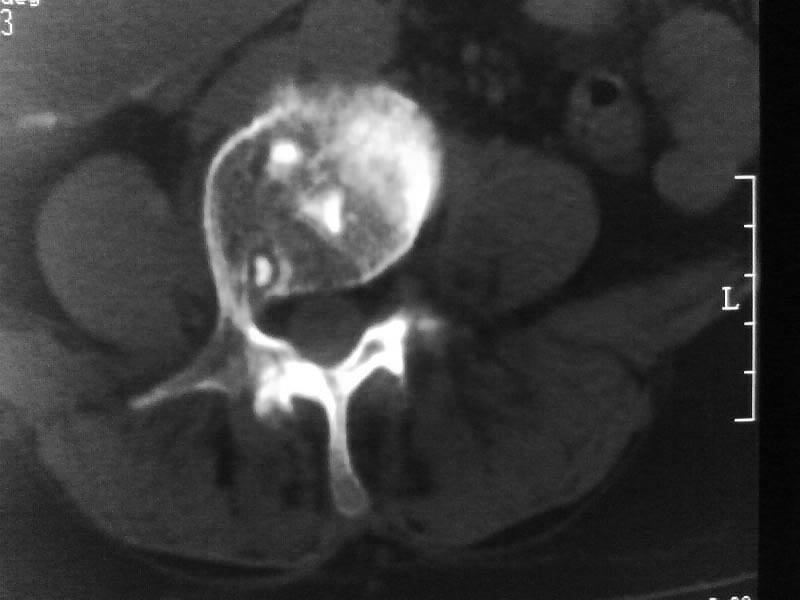

定位相示l2呈楔形改变(ct示陈旧性骨折改变,图像未传),l4.5椎体融合,以下是l4.5ct平扫.请各位看看,

考虑结核(有破坏、硬化及死骨)。

1、三四椎体结核,2、水平骶椎。

1、l1压缩性骨折(陈旧性)。

2、l3、4椎体结核。

就是腰1压缩性骨折,腰3\\4椎体结核(融合),水平骶椎.

支持 l1椎体陈旧性压缩性骨折;l3、4椎体结核(融合);水平骶椎。